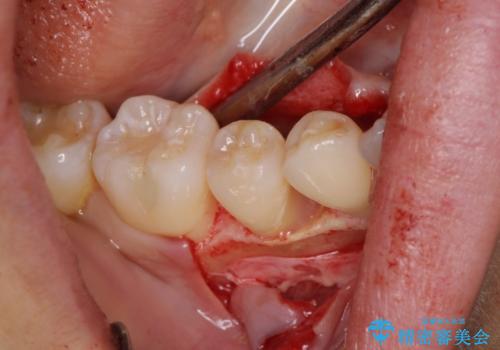

患者様は、他院で右下の歯を抜歯かもと言われました。全体の歯周病はなく、右下の1歯だけ骨が極端に減少していました(初診時歯周ポケット7mm。通常は3mm以下。)。その歯だけ咬合が強いことが原因と考えられたため、咬合を弱くする処置と減少した骨を再生する処置が必要になりました。

骨の再生治療手術をして10か月経過観察をしたのち、骨を平坦化する手術を行い、治療終了となりました。